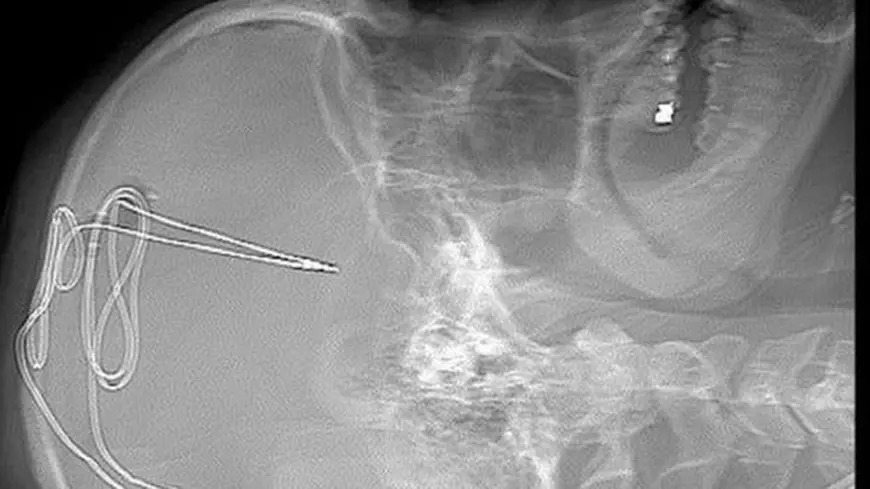

Medicii spun că operația este realizată numai în urma unei serii complexe de analize. Aceasta implică realizarea unei incizii de mici dimensiuni în craniu prin care este introdus un electrod de un milimetru. Dispozitivul este implantat într-o anumită zonă a creierului pentru a controla impulsuri, precum dependența și auto-controlul.

:contrast(8):quality(75)/https://static4.libertatea.ro/wp-content/uploads/2019/11/109580568mediaitem109580567.jpg)

WVU MEDICINE HOSPITAL / BBC

Ulterior, o baterie este introdusă sub claviculă, iar activitatea cerebrală poate fi monitorizată de la distanță de o echipă de medici, psihologi și specialiști în dependență pentru a stabili dacă apare din nou comportamentul specific adicției de droguri.